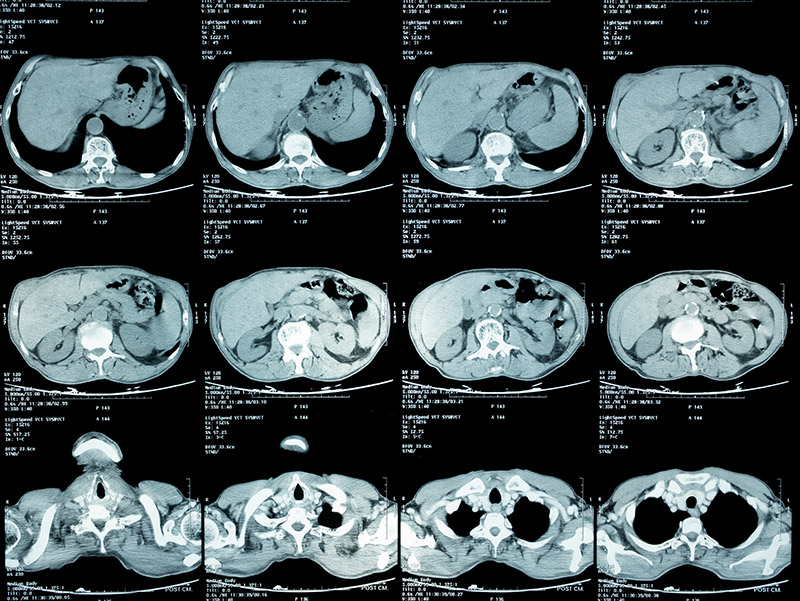

健康診断で再検査を言われ、精密検査をした結果、肺癌のステージⅣと言われました。その時は、もう何を言われたのか覚えてないですし、本当に頭が真っ白になりました。それまで、何気なく過ごしていた日常が全て失われ、何もかも嫌になりました。

それでも家族の支えもあり、少しずつ治療に前向きになり、抗がん剤治療などを受けましたが、残念ながら効果はありませんでした。副作用が強く、心も体も限界で抗がん剤治療をするくらいなら、もうステージⅣの悪性腫瘍が改善小さくなった画像を見て涙が止まりませんでした。死んでもいいと思っていました。

そんな時に私の友人から紹介され、松田先生に藁にもすがる思いで治療をお願いしました。私自身が治ることに諦めていましたが、松田先生は真摯に話を聞いてくれて、一生懸命治療をしてくれました。6ヶ月が経過した写真を見た時に、私でもわかるくらいにガンが小さくなっているのがわかりました。病院の先生の説明を聞きながら、涙を止まらなかったのを今でも覚えています。